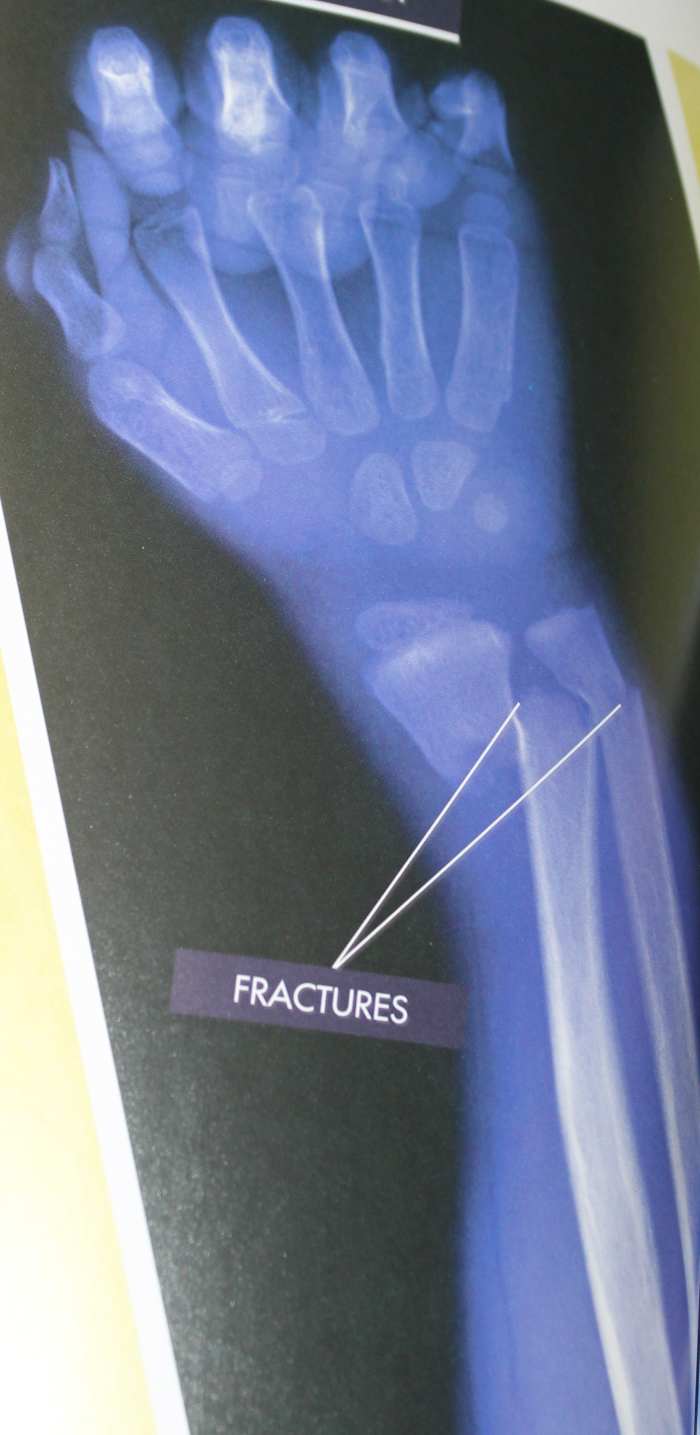

X-Ray of a Fracture from the below book “Your Body Battles a Broken Bone”

Part 6: How Broken Bones Heal

- X-ray or picture of an x-ray

- Show an x-ray or a picture of an x-ray. Pass around a cast if someone has one.

- Say, “A bone is strong like steel and concrete, but the spongy bone makes the bone resilient so that it can bounce back after being compressed. There is one main difference in this living tissue when compared to other matter. It has the ability to repair itself. A bone will start healing within one hour of a fracture. That’s why it is an emergency when someone breaks a bone. As soon as possible, x-rays need to be taken to see if surgery is required to put the two bones back together.”

- Tell them, “Within one hour of a fracture, leaking blood from the bone forms a blood clot. After a few days, cells called fibroblasts and osteoblasts make spongy bone in the open area. A callus forms on the bone as it continues to harden and blood vessels regrow over the area. It will continue to harden and be completely healed in 3 months.”